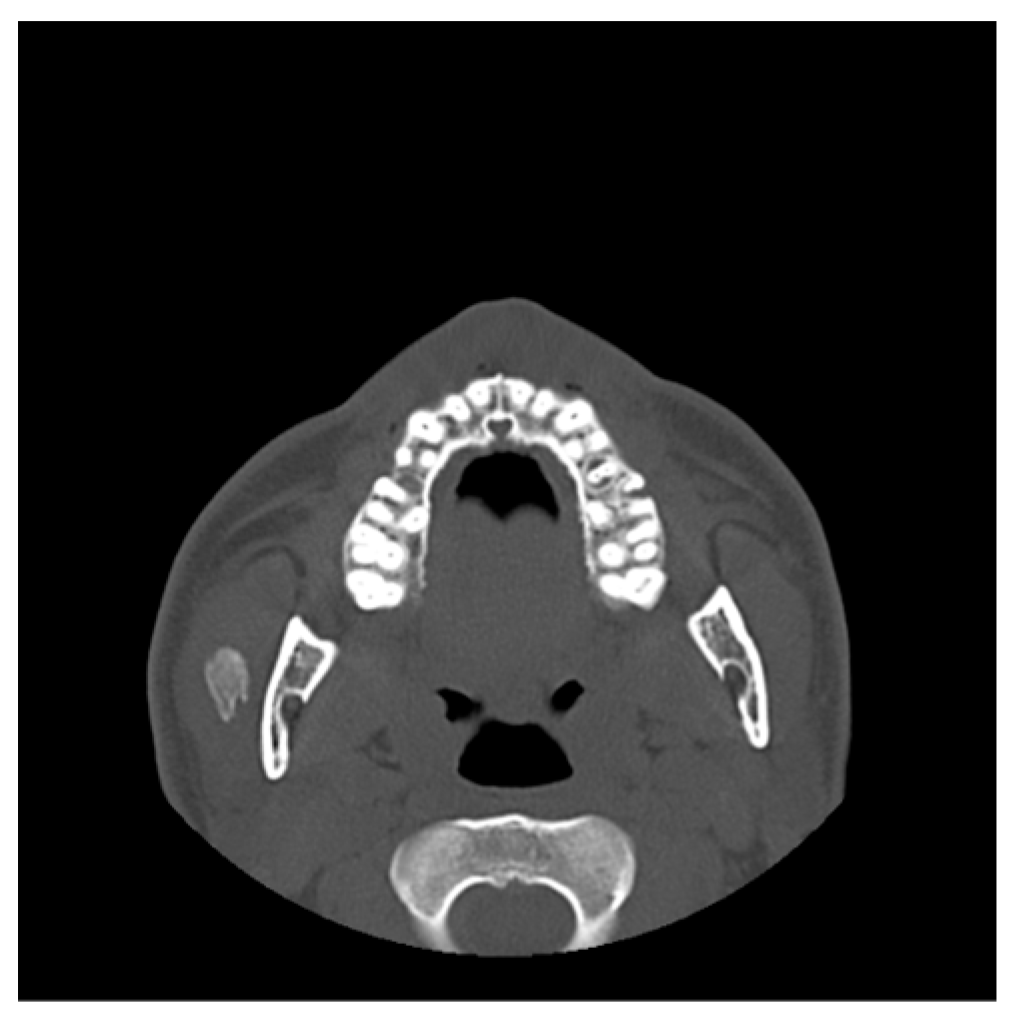

- Case 1

- Case 2

- Case 3

- Case 4

- Case 5